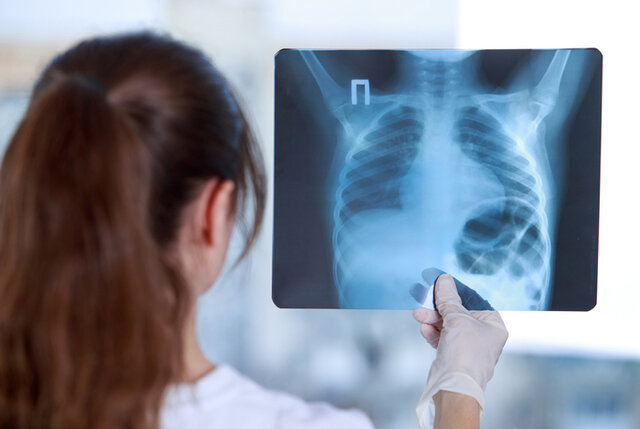

Técnicas de imágenes diagnósticas

realizaba experimentos con tubos de vacío y un generador eléctrico. Con el hallazgo de este haz de luz capaz de atravesar la materia, nació el diagnóstico médico por imágenes que mejoró considerablemente el ejercicio de la medicina.

En el año 1972, fue creada y desarrollada La tomografía computada (TC) por Godfrey Hounsfield, construyó una máquina que utilizaba los rayos X para hacer imágenes tridimensionales del interior del cuerpo, y permitir a los médicos una visión transversal de los órganos, huesos y tejidos.

En 1989, surge la tomografía computada helicoidal, la cual tenía ventajas considerables a su antecesora la Tomografía Axial Computada (TAC). Ya que permitía la adquisición continua de varias imágenes por cada inspiración.

nace la tomografía computada multidetector, también conocida como multislice (TCMS), el avance en esta técnica es que ya contaban con varias filas de detectores (4 filas para los primeros equipos de este tipo) los cuales iban en aumento conforme se perfeccionaba el diseño y técnica del instrumento hasta llegar actualmente a encontrar tomógrafos con 64 filas de detectores; es importante resaltar que a mayor número de filas de detectores los resultados son mejores